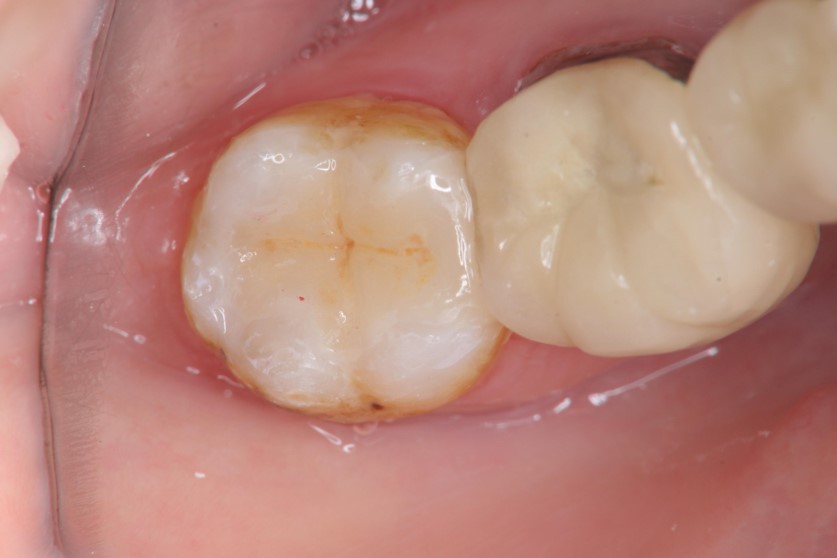

治療後口內照

治療後密合度良好